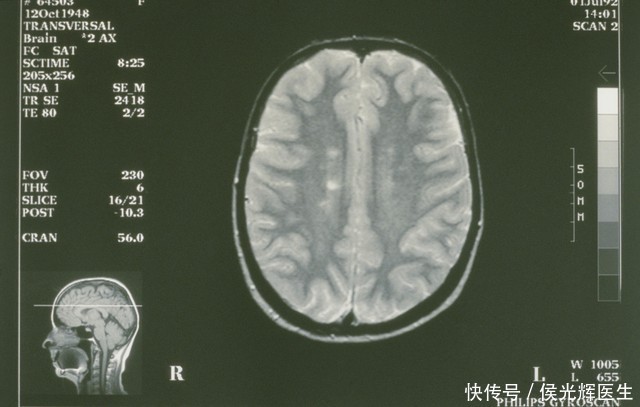

我们常把大脑想象成一个精密而强悍的器官,却忽略了它的运作完全依赖于一套复杂又精细的“生命补给线”——血管系统。脑卒中本质上就是这条补给线发生的紧急事故。可能是血管被堵塞,就像水管被杂物堵住,血液无法流过;也可能是血管壁破裂,如同水管爆裂,血液外溢。无论哪种情况,结果都是大脑的某个区域突然陷入“断粮断电”的困境。那里的神经细胞在几分钟内就开始受损,它们所负责的功能——可能是你抬起手臂的动作,可能是你说出一句完整话语的能力,也可能是你保持平衡的感觉——便会随之出现问题。